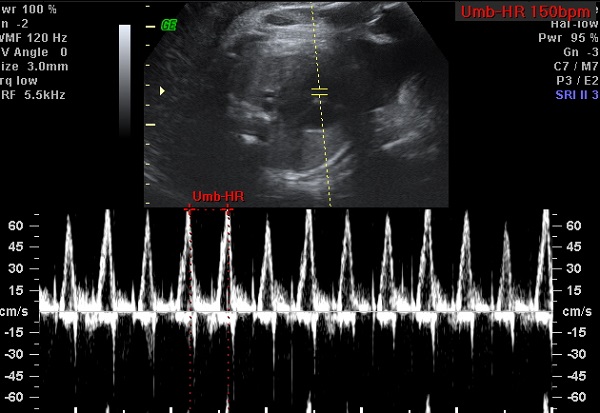

When we found out the gender of our baby, we went to a 3D ultrasound place. We were given a coupon to come back for a discounted rate to have another one done at 30 weeks. We came back and found that the baby was Frank breech and couldn’t really get any good pictures. So they rescheduled one for today. We left Barnes and Nobel and met Sam at the ultrasound place. The good news is that the baby had flipped out of the breech position. The bad news was that she was sleeping and not in a good place for us to see her. They gave Sam juice in hopes that the sugar would wake her up. She drank the juice and we even took a walk around outside. When we came back, we still couldn’t get a good picture of her face. They were, however, able to record her heartbeat for us.

I thought Sam was going to throw up during it. The lady was really trying to get the baby to wake up. She kept rubbing Sam’s belly and poking and massaging her, but the baby would not move. We did get a semi-good profile shot. We also got to see that she has a lot of hair. We got a neat shot of her hand kind of making a fist, but NO good face picture. I admit, I was disappointed. I wanted to be able to take the 3D picture of her face and compare it with her birth picture like so many parents do, but I guess we just need to wait and see her beautiful face when she arrives.